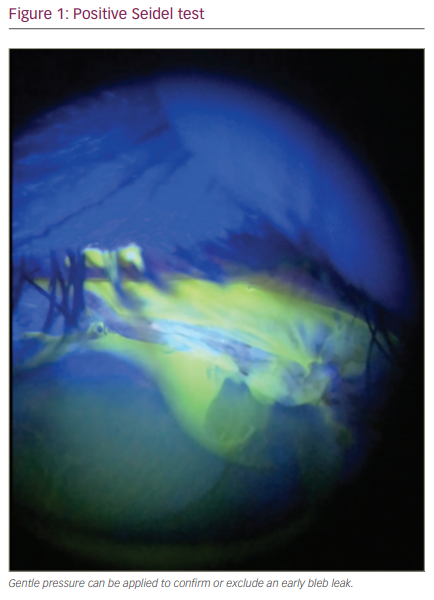

이때는 안압이 낮고, 여과포가 납작해져있고, Seidel test에서 창상누출이 관찰됩니다.